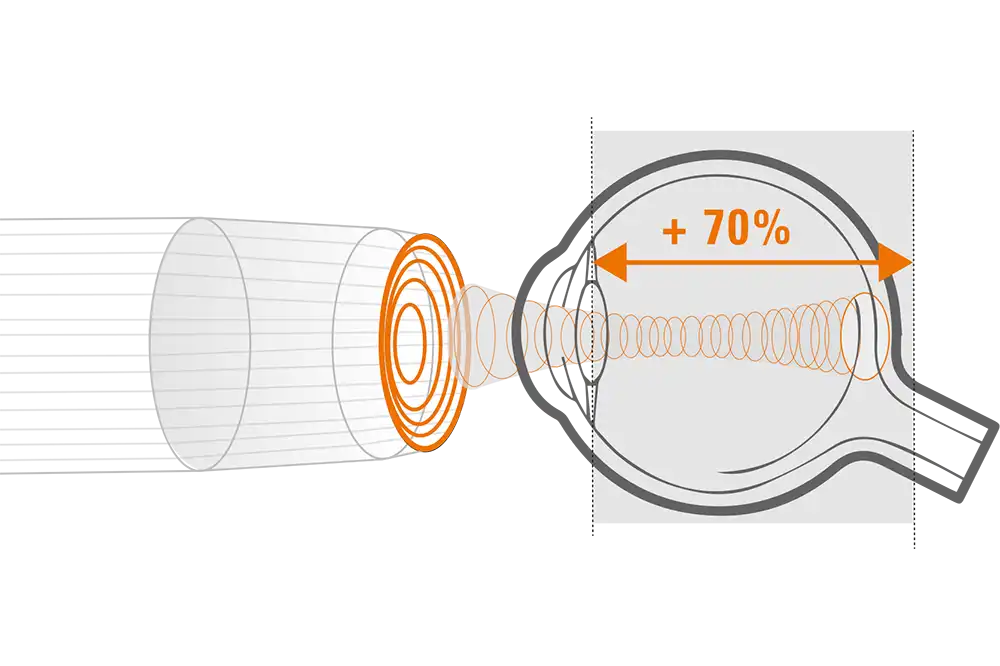

Quantel Medical heeft een sprong voorwaarts gemaakt met de nieuwe technologie met 5 ringen op een 20 MHz-sonde. Het principe is om om en om ultrasone geluidsgolven uit te zenden via 5 concentrische transducers in dezelfde sonde. Deze technologie:

- Verhoogt het focusgebied

- Vermindert de laterale resolutie van 250 naar 200 µm, oftewel met 25%

- Behoudt een hoge axiale resolutie

Verlengde scherptediepte van 70%

De ringtechnologie verdubbelt praktisch de scherptediepte. De 20 MHz-ringvormige sonde heeft een verlengde scherptediepte van 70%, waardoor het mogelijk is om pathologieën van het glasvocht, het netvlies en verder tegelijkertijd te observeren zonder concessies te doen aan de beeldresolutie.